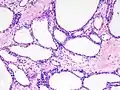

Micrograph showing a pancreatic serous cystadenoma. H&E stain.